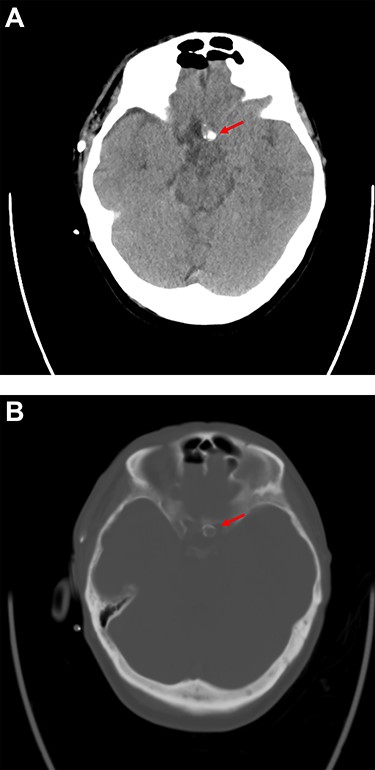

Postoperative cranial computed tomography (CT) showed massive calcification of the aneurysm neck and dome with adherence to the skull base at the level of the tuberculum sellae; the CT results corresponded well to the intraoperative findings (Fig. 3A and B).

Postoperative computer tomography (A. soft tissue window, B. bone window) shows calcification of the aneurysm neck and dome with adherence to the skull base at the level of the tuberculum sellae.